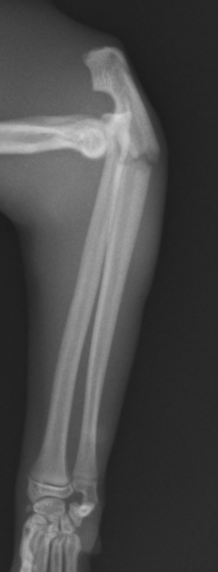

術後はすぐに足を着いてくれて骨の癒合も進んで行きました。猫は手を捻ってものを掴んだりする動作が多いため、尺骨と橈骨を固定しているスクリューは早めに抜去しなくてはなりません。その後に骨が癒合したらインプラントを全て抜去します。

全てのインプラントを抜去しました。手の向きや骨の状態も問題ありませんので、終了となります。